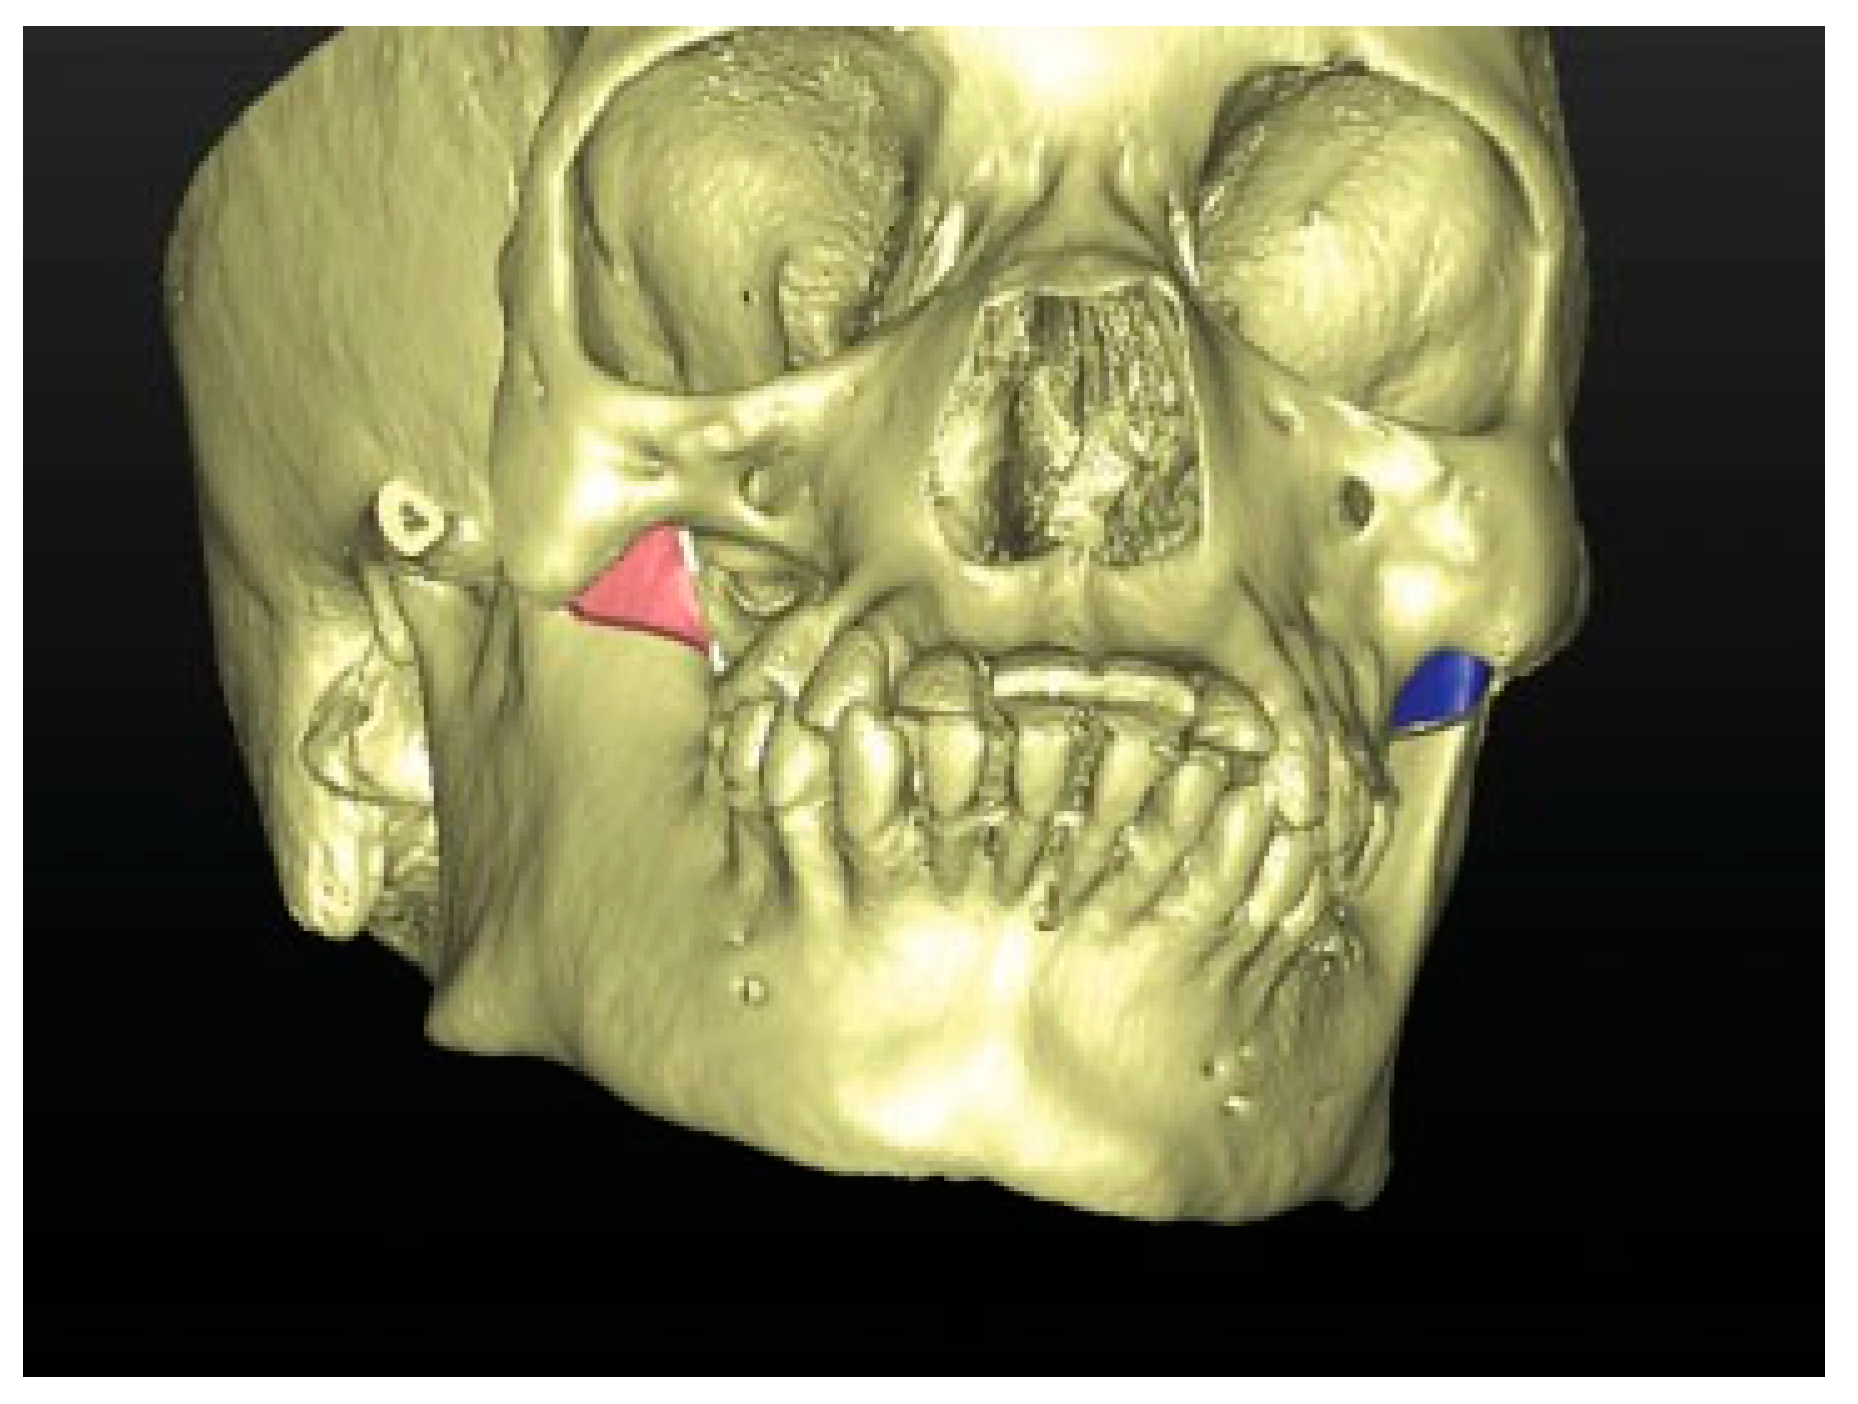

Figure 5. CT scan with 3D reconstruction: upper and lower jaw dental collapse with labioversion, dental agenesis, and right hemifacial microsomia.

A CT scan of the head with 3D reconstruction (Figure 1, Figure 2, Figure 3, Figure 4 and Figure 5) confirmed a maxillomandibular fusion associated with a cleft palate, agenesis of the right turbinate, and right hemifacial microsomia (Laster type 2b syngnathia). Both temporomandibular joints (TMJs) were normal and showed no bony ankylosis (fibrous ankylosis could not be excluded with the given data).

A facial angio-CT scan was performed to study cervical vascular anatomy and to discard anatomical variants at the level of the internal maxillary artery. Heteroanamnesis revealed a family history of endogamy and second-degree consanguinity. 3D planning of the surgery was performed with SimPlant O&O (Materialise Dental/Dentsply Implants, Mölndal, Sweden) to study the patient’s anatomy and design the necessary osteotomies to separate the jaws (Figure 6 and Figure 7). Thanks to the 3D preparation, the surgical access could be decided on an intraoral approach with sufficient exposure to do the osteotomy and ostectomy seemed feasible. In case the access was insufficient, a hemicoronal approach with osteotomy of the zygomatic arch had to be considered.

This patient can be considered as a complex zygomaticomandibular syngnathia or type 2b, because of the bony fusion of the mandible to the zygomatic complex associated with a palatal cleft, hemifacial microsomia, agenesis of the right turbinate, and dental agenesis (elements 15, 16, 17, and 18). The patient has the highest age at diagnosis described in the literature.